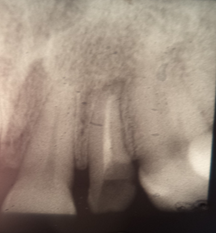

The patient I.M., 32 years old, presented for the restoration of the severely damaged upper right lateral incisor (tooth 12) following trauma (Figure 1).

Figure 1: Initial Situation.

She also exhibits anterior diastemas. The periapical radiograph reveals insufficient endodontic treatment and a periapical lesion (Figure 2).